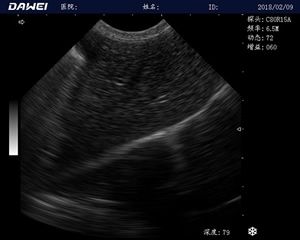

MT15獸用B超機適用探頭

適用對象:

牛羊馬豬犬貓及多種家禽、實驗動物、野生動物、及部分水生動物

應用范圍:

中小動物的肝、膽,脾、腎、膀胱、子宮、妊娠等各組織器官的檢查和病變的診斷